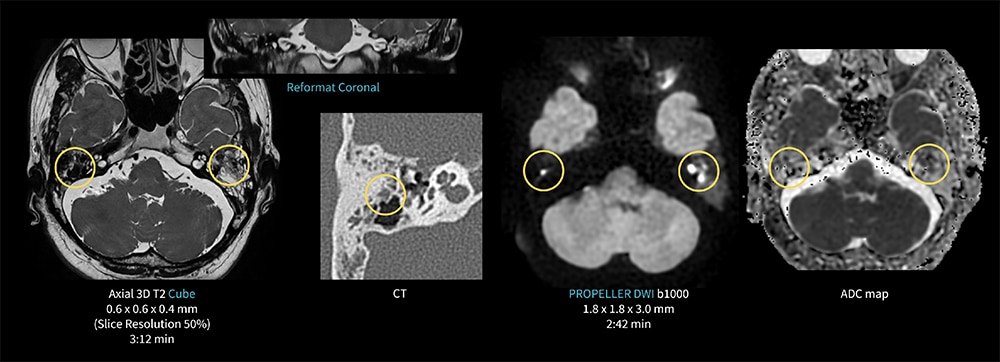

Case3 Cube & PROPELLER DWI/真珠腫

40代、男性。左耳閉感にて左中耳真珠腫疑いのため聴神経MRI検査を施行した。

Thin sliceやReformatでの観察のため、AIR Recon DLを併用した3D Cubeを撮像し、磁化率アーチファクトを抑えるため、DWIはAIR Recon DLを併用したPROPELER DWIを撮像。

空気による歪みを抑え、左鼓室から乳突洞に真珠腫、さらには右乳突蜂巣内の真珠腫が明瞭に高信号として確認された。

図3 CubeとPROPELLER DWIを用いた真珠腫の描出